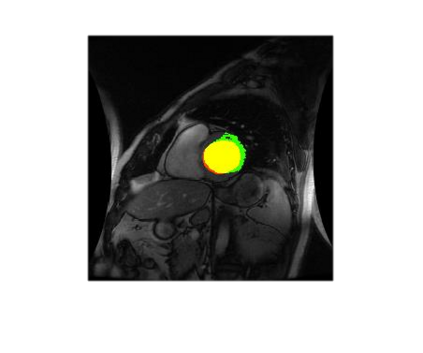

Deep Convolutional Neural Networks (DCNNs) are used extensively in biomedical image segmentation. However, current DCNNs usually use down sampling layers for increasing the receptive field and gaining abstract semantic information. These down sampling layers decrease the spatial dimension of feature maps, which can be detrimental to semantic image segmentation. Atrous convolution is an alternative for the down sampling layer. It increases the receptive field whilst maintains the spatial dimension of feature maps. In this paper, a method for effective atrous rate setting is proposed to achieve the largest and fully-covered receptive field with a minimum number of atrous convolutional layers. Furthermore, different atrous blocks, shortcut connections and normalization methods are explored to select the optimal network structure setting. These lead to a new and full-scale DCNN - Atrous Convolutional Neural Network (ACNN), which incorporates cascaded atrous II-blocks, residual learning and Fine Group Normalization (FGN). Application results of the proposed ACNN to Magnetic Resonance Imaging (MRI) and Computed Tomography (CT) image segmentation demonstrate that the proposed ACNN can achieve comparable segmentation Dice Similarity Coefficients (DSCs) to U-Net, optimized U-Net and hybrid network, but with significantly reduced trainable parameters due to the use of full-scale feature maps and therefore computationally is much more efficient for both the training and inference.